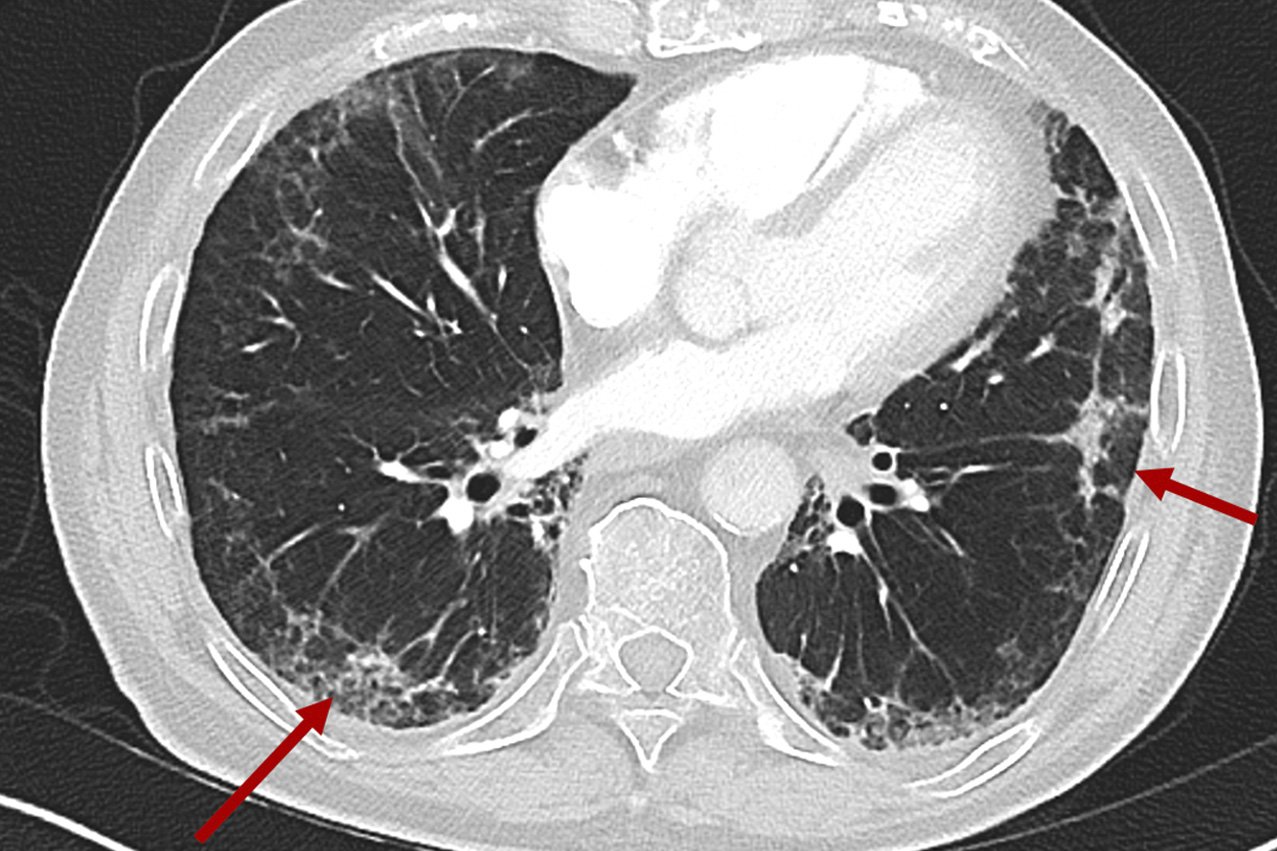

Hochmoderne Technik für Lungenfunktionsdiagnostik, Belastungsuntersuchungen (Spiroergometrie, 6-Minuten-Gehtest), Allergiediagnostik, Ultraschall von Brustkorb und Lunge inklusive Ultraschall-gestützte Punktionen, Röntgen, Computertomographie und Bronchoskopie unterstützt uns bei einer exakten Diagnostik. So können wir Therapiekonzepte für Patient*innen entwickeln, die individuell auf deren Erkrankungen ausgerichtet sind und den aktuellen Leitlinien folgen.

Wichtig ist eine genaue Abklärung, um welche Art einer Lungenfibrose es sich handelt. Hierfür sind eine Computertomographie (CT) der Lunge, Blutuntersuchungen und in vielen Fällen auch eine Spiegelung der Atemwege (Bronchoskopie) nötig. Unklare Fälle besprechen wir in einer Spezialkonferenz mit dem Klinikum Großhadern.

Computertomographie

Die hochmoderne Computertomographie (CT) in der Augustinum Klinik steht Privatpatient*innen oder Selbstzahler*innen auch zur ambulanten Diagnostik in der Fachabteilung Pneumologie zur Verfügung. Telefonische Anmeldung erfolgt über das Sekretariat.